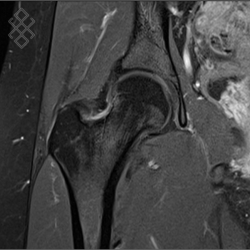

IRM de la Hanche